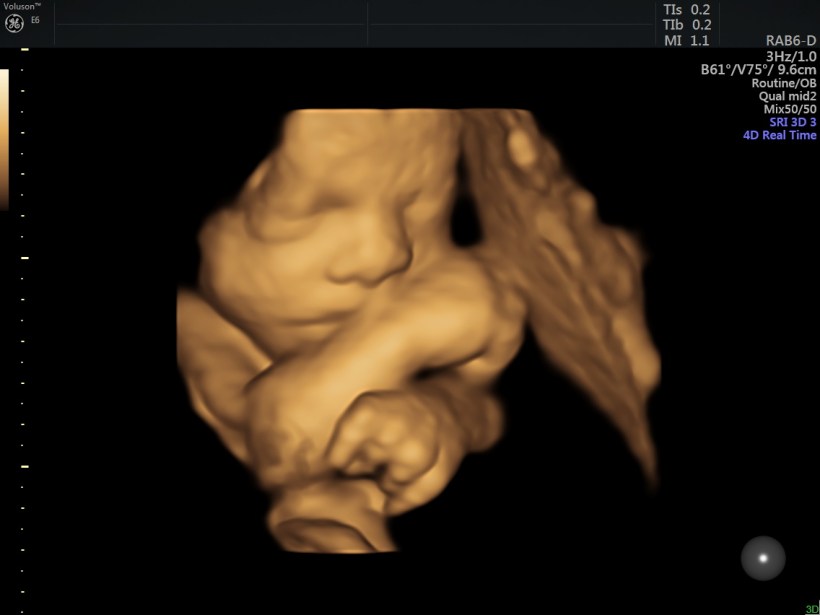

Some of you follow every blog post and I love how supportive you are for us!  Today I wanted to keep this short and sweet (extra sweet) and share some recent baby photos we received a few weeks ago!  My heart is full and just can’t wait to have this chunky little baby boy in my arms.

Image_16 (1)

Of course, like his parents he does his best to steer clear of the camera and is also a bit stubborn.  Out of the 50 photos we received, these were the ones we could see his sweet face the most.  Although chunky and adorable, he is mighty!  🙂